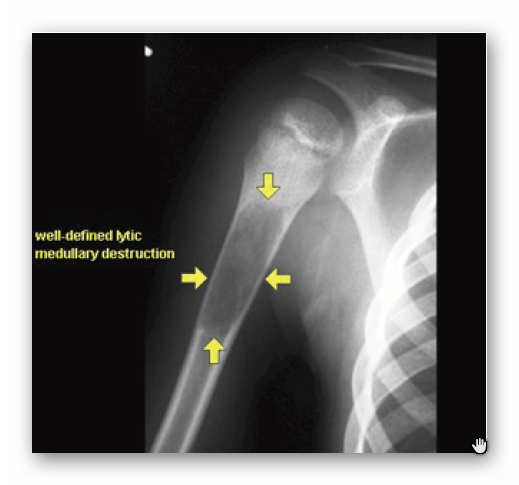

TORBIEL MŁODZIEŃCZA

RTG